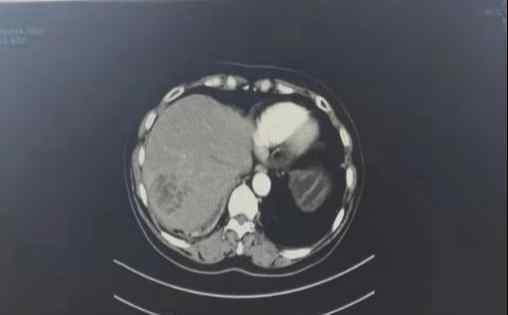

近日,我院急诊外科主任杨念斌与肿瘤科主任张贡献合作,完成了一次CT引导下经皮肝脓肿引流。

患者马某因“发热、咳嗽、恶心、呕吐3天”入院。相关检查有所改进,血培养呈革兰氏阴性菌。诊断:1。肝脓肿2。肺部感染3。菌血症4。右侧胸腔积液。经多学科会诊,CT引导下经皮肝脓肿引流,手术过程顺利。术后通过引流管多次冲洗给药,治疗效果良好,患者恢复良好。